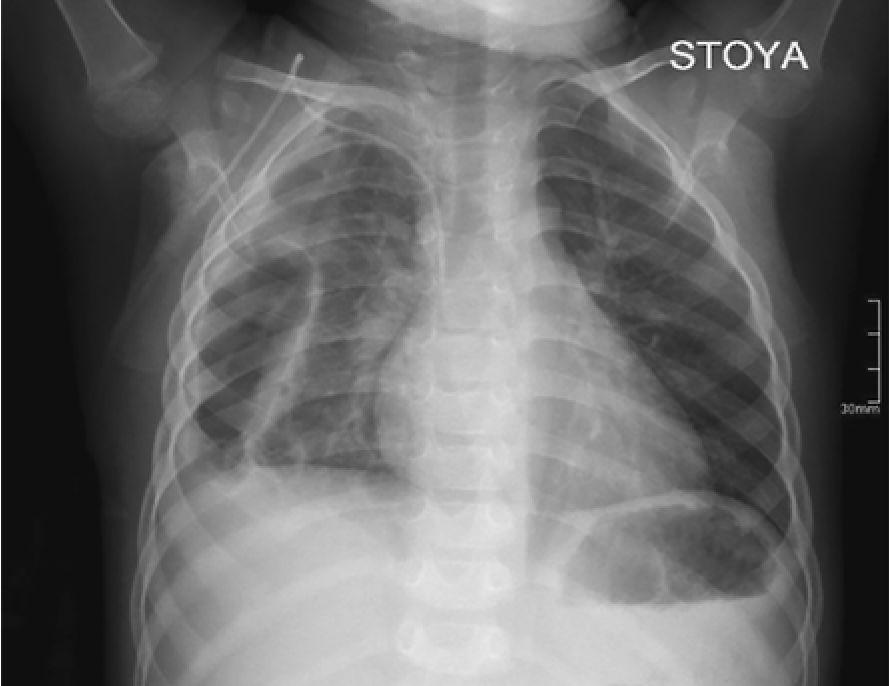

На третий день болезни при рентгенографии органов грудной клетки выявлено снижение прозрачности левого легочного поля в базальном отделе (инфильтративные изменения), а также небольшое количество выпота в левой плевральной полости с затенением реберно-диафрагмального синуса (рис. 1).

Рис. 1. Рентгенограмма органов грудной клетки в прямой проекции мальчика Б. на третий день болезни. Левосторонняя нижнедолевая пневмония, левосторонний гидроторакс минимального объема